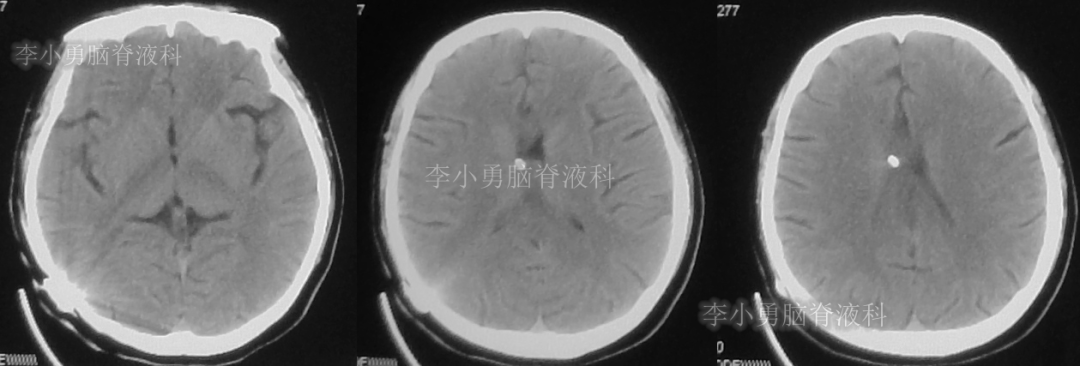

此后1个多月(2019年11月4日到2019年12月16日),患者意识一直无改善,一直呈模糊状态,多次复查头颅CT(图-12至图-20)见脑室大小反复变化不定,医生根据CT结果等反复多次调节分流泵压力(具体过程家属回忆不起)。但患者病情无好转却逐渐加重,逐渐不能咀嚼、吞咽及进食,卧床不起。

图-12:2019年11月8日头颅CT

图-13:2019年11月16日头颅CT

图-14:2019年11月19日头颅CT

图-15:2019年12月3日头颅CT

图-16:2019年12月10日头颅CT

图-17:2019年12月12日头颅CT

图-18:2019年12月13日头颅CT

图-19:2019年12月14日头颅CT

图-20:2019年12月16日头颅CT